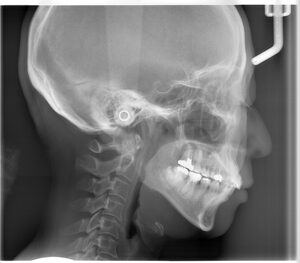

顎の関節の変形

初診時のレントゲンです。一番後ろの歯のさらに奥に親指のような形のようなものが見えます。これが顎の関節です。左右一対で対照的な形を本来はしています。向かって左は丸く普通の形をしていますが、右の顎の関節の形は左に比べて小さくなっています。左のかみ合わせの高さが低くなっていることで、下顎が右の奥に押し込まれています。そのことで顎の関節が年月をかけて変形していると考えられます。顎の関節が定位置にいられないことで顎の開閉口でカクっと鳴ったり、痛みを生じます。顎関節症の原因にはいろいろな原因が考えられていますが、かみ合わせが原因とされる顎関節症のメカニクスは述べた通りです。顎の関節の後ろには血管、神経が通っています。顎の関節が後ろに押し込まれることでその部分を圧迫してしまいます。その圧迫が片頭痛の原因になっていることもあります。ほうれい線もかみ合わせの高さが低くなっている方が深くなります。左右差が出るのはこういった理由です。かみ合わせ高さを含めて改善され、下顎が本来の位置に戻ることができれば、時間はかかりますが顎関節の形は年齢に関係なく戻っていくと報告されています。

頸椎の変化

少しわかりづらいですが、頸椎の角度が治療につれ少し立ってきています。まだ本来と逆の反り方ですが、それでも姿勢が矯正治療することで改善されていることがわかります。頭の重さは5㎏あります。その重さをバランス取って背骨の上に載せています。かみ合わせがズレていると前後左右のバランスが崩れます。舌の位置が後ろや下にあると呼吸しやすくするための姿勢にズらしています。いろいろなズレを修正するのに身体は不均衡な筋肉の使い方をします。その結果が口の周りだけでなく遠く離れたところまで不具合を生じさせてしまうのです。